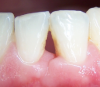

lyubovmuzgina Опубликовано 2 июня, 2013 Поделиться Опубликовано 2 июня, 2013 Как восстановить межзубной сосочек между 31-41.Результат ортодонтического лечения. Ссылка на комментарий

lyubovmuzgina Опубликовано 2 июня, 2013 Автор Поделиться Опубликовано 2 июня, 2013 точно! ну так на одном симпозиуме были ))сосочка нет совсем, визуально - равнобедренный треугольник с ровным основанием слизистой Ссылка на комментарий

lyubovmuzgina Опубликовано 16 июня, 2013 Автор Поделиться Опубликовано 16 июня, 2013 Пожалуйста фото. Ссылка на комментарий

sergio Опубликовано 16 июня, 2013 Поделиться Опубликовано 16 июня, 2013 Пожалуйста фото.боюсь, гиалуронка здесь не поможет. Надо еще ортодонту работать... хирургически тоже такое не закрыть... А что, пациентку это волнует? это же неэстетически значимая зона обычно Ссылка на комментарий

Bier Опубликовано 16 июня, 2013 Поделиться Опубликовано 16 июня, 2013 хирургически - неоперабельно, костного пика нет. Виниры + ССТ несколько улучшат ситуацию. 3 Ссылка на комментарий